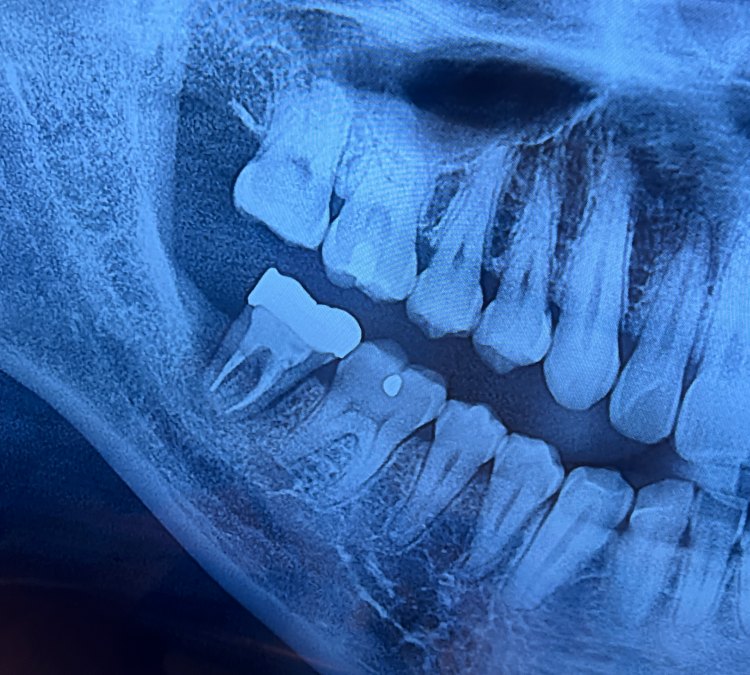

오랜만에 찾은 치과는 정말 낯설었습니다. 이전에 어렵게 살려서 이 모양으로 씌어 놓은 크라운 속에 염증이 차서 잇몸이 녹고 있으며 이를 뽑아야하는 지경에 이르렀다는 것입니다.

신경치료 할때 너무 힘들고 고통스러웠기 때문에 겁부터 났습니다. 엑스레이는 멀쩡해 보이는데 수술하지 말까?

치아뿌리가-가늘어져있는-치아-x레이-사진

치아 속 잇몸이 다른 것들에 비해 많이 약해져 있다.